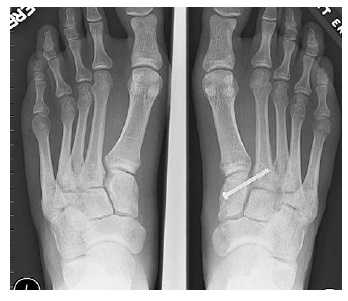

(Слева) На рентгенограмме, выполненной без нагрузки, не видно каких-либо признаков повреждения сустава Лисфранка. (Справа) На рентгенограмме в положении стоя мы видим увеличение расстояния между костями, свидетельствующее в повреждении связок сустава Лисфранка.

В случаях этого повреждения показано оперативное лечение, открытое устранение подвывиха основания 2 плюсневой кости с фиксацией винтом. Устранение подвывиха производится из доступа в 1 межплюсневом промежутке, рубцовая ткань и остатки связки могут интерпонировать сустав, тогда потребуется их удалить. После вправления производится предварительная фиксация спицей и рентгенологический контроль.

Затем устанавливается винт соединяющий основание 2 плюсневой кости и медиальную клиновидную кость.